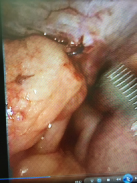

Contrast-enhanced CT was not done as the condition was very obvious clinically. He was taken up for diagnostic laparoscopy under general anesthesia which showed herniation of distal small bowel loop through a peritoneal defect of the previous hernioplasty site with dense adhesions of the bowel to the mesh .The herniated bowel was reduced, the hernia defect was dealt with closure by direct stitching and glue again of the mesh to the abdominal wall after aspiration of the reactionary fluid, stitching itself was not an easy task because of the friability and thinness of the peritoneal flap and this is why a glue is used. The patient had an uneventful recovery and was discharged on the fourth post-operative day. The patient underwent follow-up examination 21 days after discharge and did not have any significant abnormality.1–3

Figure 4 Small bowel loop adherent to the defect